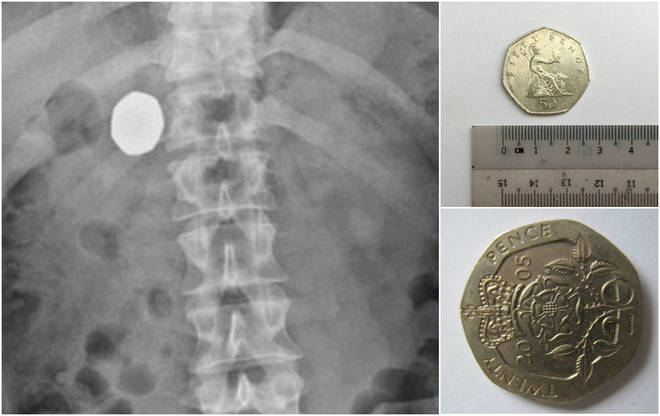

Ele decidiu visitar um médico ao não conseguir regurgitar a moeda maior, de 2,5 cm e valor de 50 centavos de libras

Um exame de raio x revelou que a moeda estava mesmo presa no corpo do rapaz

Em novos exames, foi detectado que as moedas ainda estavam no estomago do rapaz. Para piorar, elas haviam passado pela mucosa gástrica, algo que os médicos nunca haviam visto anteriormente